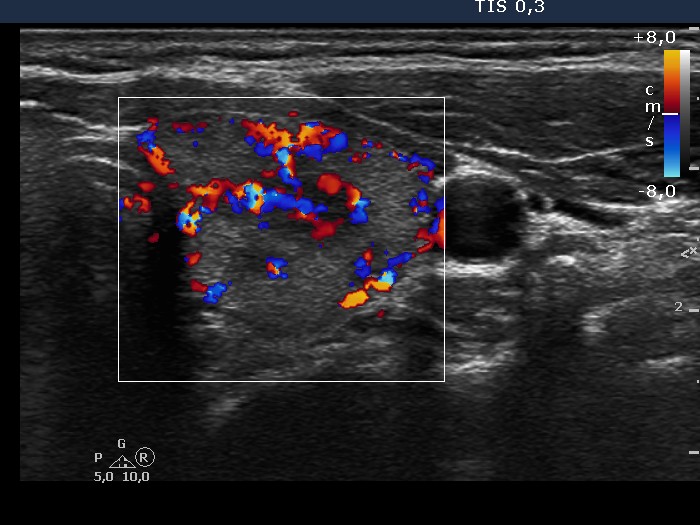

Graves' disease - Case 11.

Initial investigation (ultrasonographic picture 6)

Left lobe, horizontal scan, color Doppler mode. The blood flow is increased.